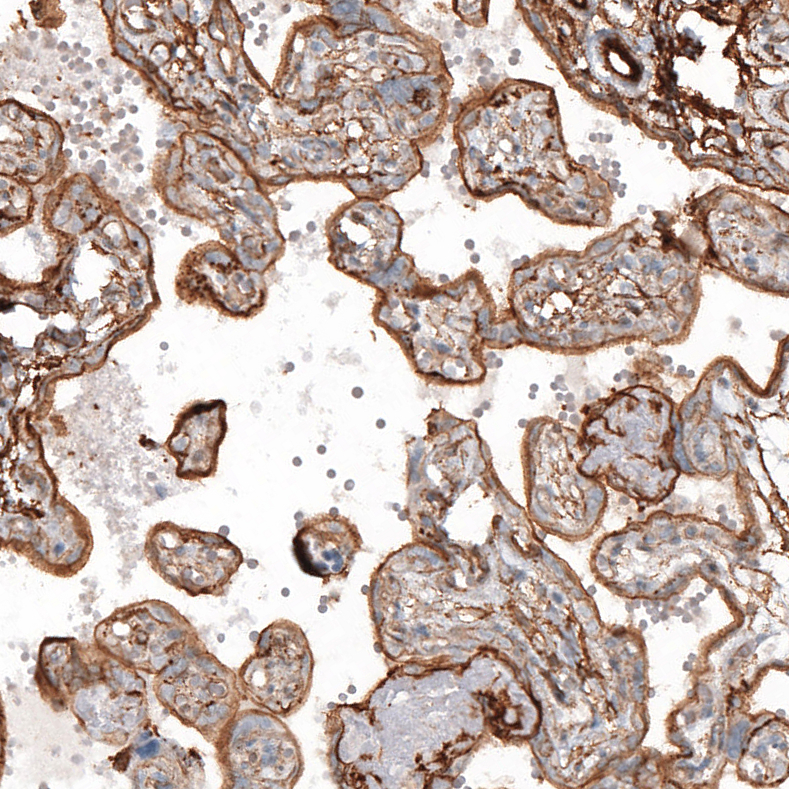

Immunohistochemical staining of human lung shows moderate cytoplasmic positivity in macrophages.